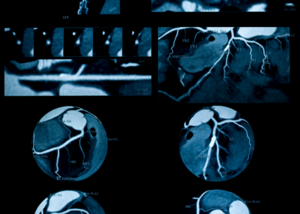

Coronary Angiography | Dr. Mehul Rathod

Heart disease continues to be one of the leading causes of death in India. Early diagnosis and timely intervention are crucial in preventing major ...